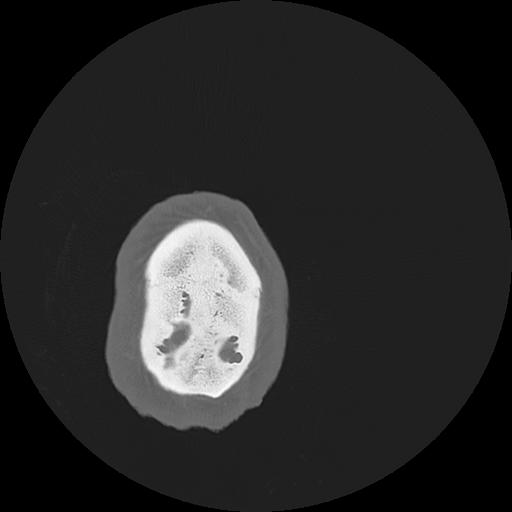

7 HUESO,,Vol,0.5,HUESO,,